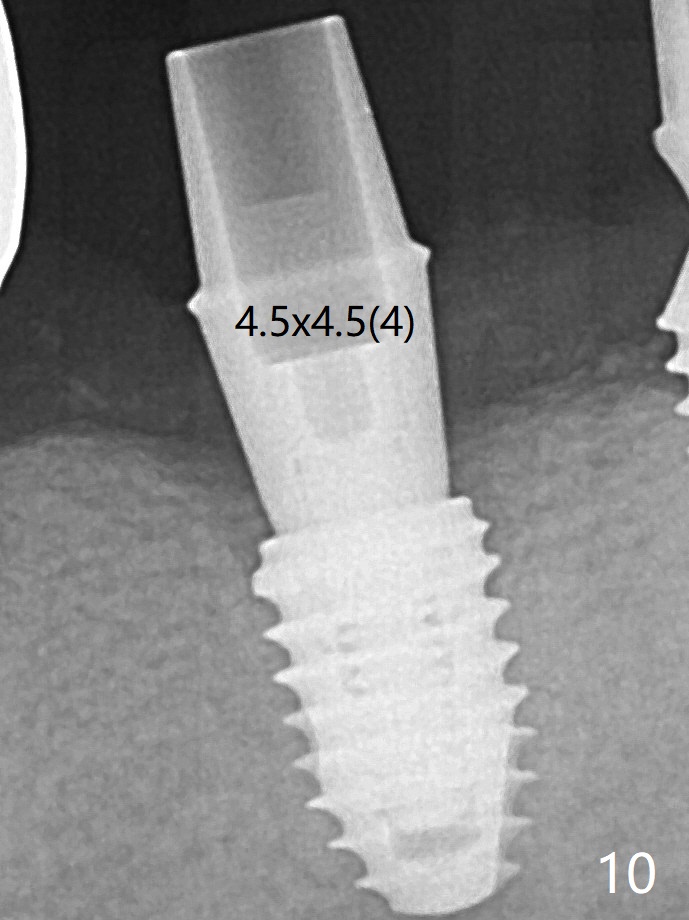

Since there is ~ 2 mm bone apical to the 5x8 mm loose implant at #19 (Fig.1), primary stability is achieved for a 4.5x10 mm dummy IS implant (having better surface treatment than the previous implant) when osteotomy is finished with a 4 mm drill (Fig.2). It is the same associated with a 4.5x7.3 mm definitive one with apical space (Fig.3 *). After depth adjustment to make sure that the implant is subcrestal circumferentially, sticky bone is placed on the top of the implant and around the implant at #18 (Fig.4 *), followed by PRF membranes and suturing with 5-0 PGA and 4-0 Chromic gut suture. Periodontal dressing is applied around the cemented abutment at #18 for additional retention. There is no paresthesia postop. In fact immediate implant redo is fairly safe. The wound heals 1 month postop (Fig.5). There is reorganized bone coronal to the healing screw 4 months postop (Fig.6), which is confirmed in uncovering. One month post uncover, the 6x4 mm healing abutment is found to be loose, suggesting incomplete seating after uncover. A 5.2x4.5(4) mm cemented abutment seems to be incompletely seated (Fig.7). It remains the same after 5.5 and 6.0 mm profile drills (Fig.8,9). A 4.5x4.5(4) mm abutment appears to be completely seated (Fig.10). When the crowns of #18 and 19 are cemented, the gingival embrasure between them is narrow (Fig.11 ^) because of bulky porcelain build-up (*). The tooth #21 with buccal Class V defect (Fig.12 *) seems to have occlusal trauma 1 year 6 months post cementation of #18 and 19. The problems are subsequently taken care of.